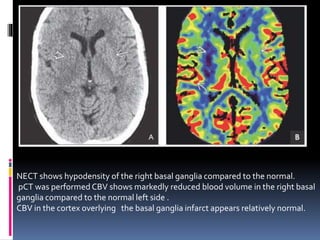

NECT shows hypodensity of the right basal ganglia compared to the normal.

pCT was performed CBV shows markedly reduced blood volume in the right basal

ganglia compared to the normal left side .

CBV in the cortex overlying the basal ganglia infarct appears relatively normal.